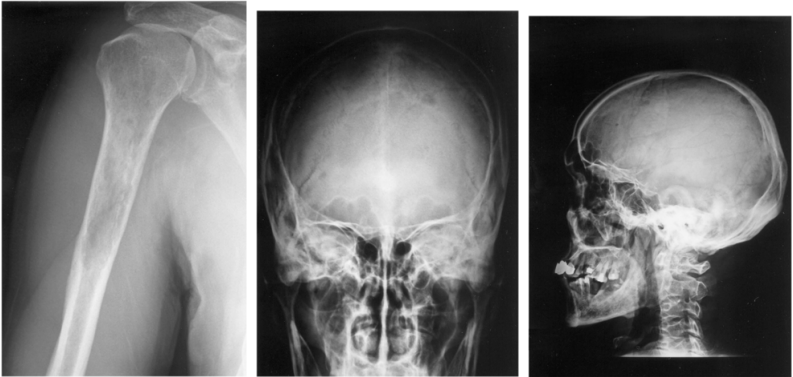

60 一位 58 歲男性,出現肱骨及顱骨等部位之腫瘤如下圖所示,且血清電泳出現異常蛋白質,則下列敘 述何者正確?

(A)很少合併發生胸椎蝕骨性病灶 (B)經常會發生病理性骨折 (C)經常合併出現低血鈣和肝功能異常 (D)主要治療方式為輻射治療和手術